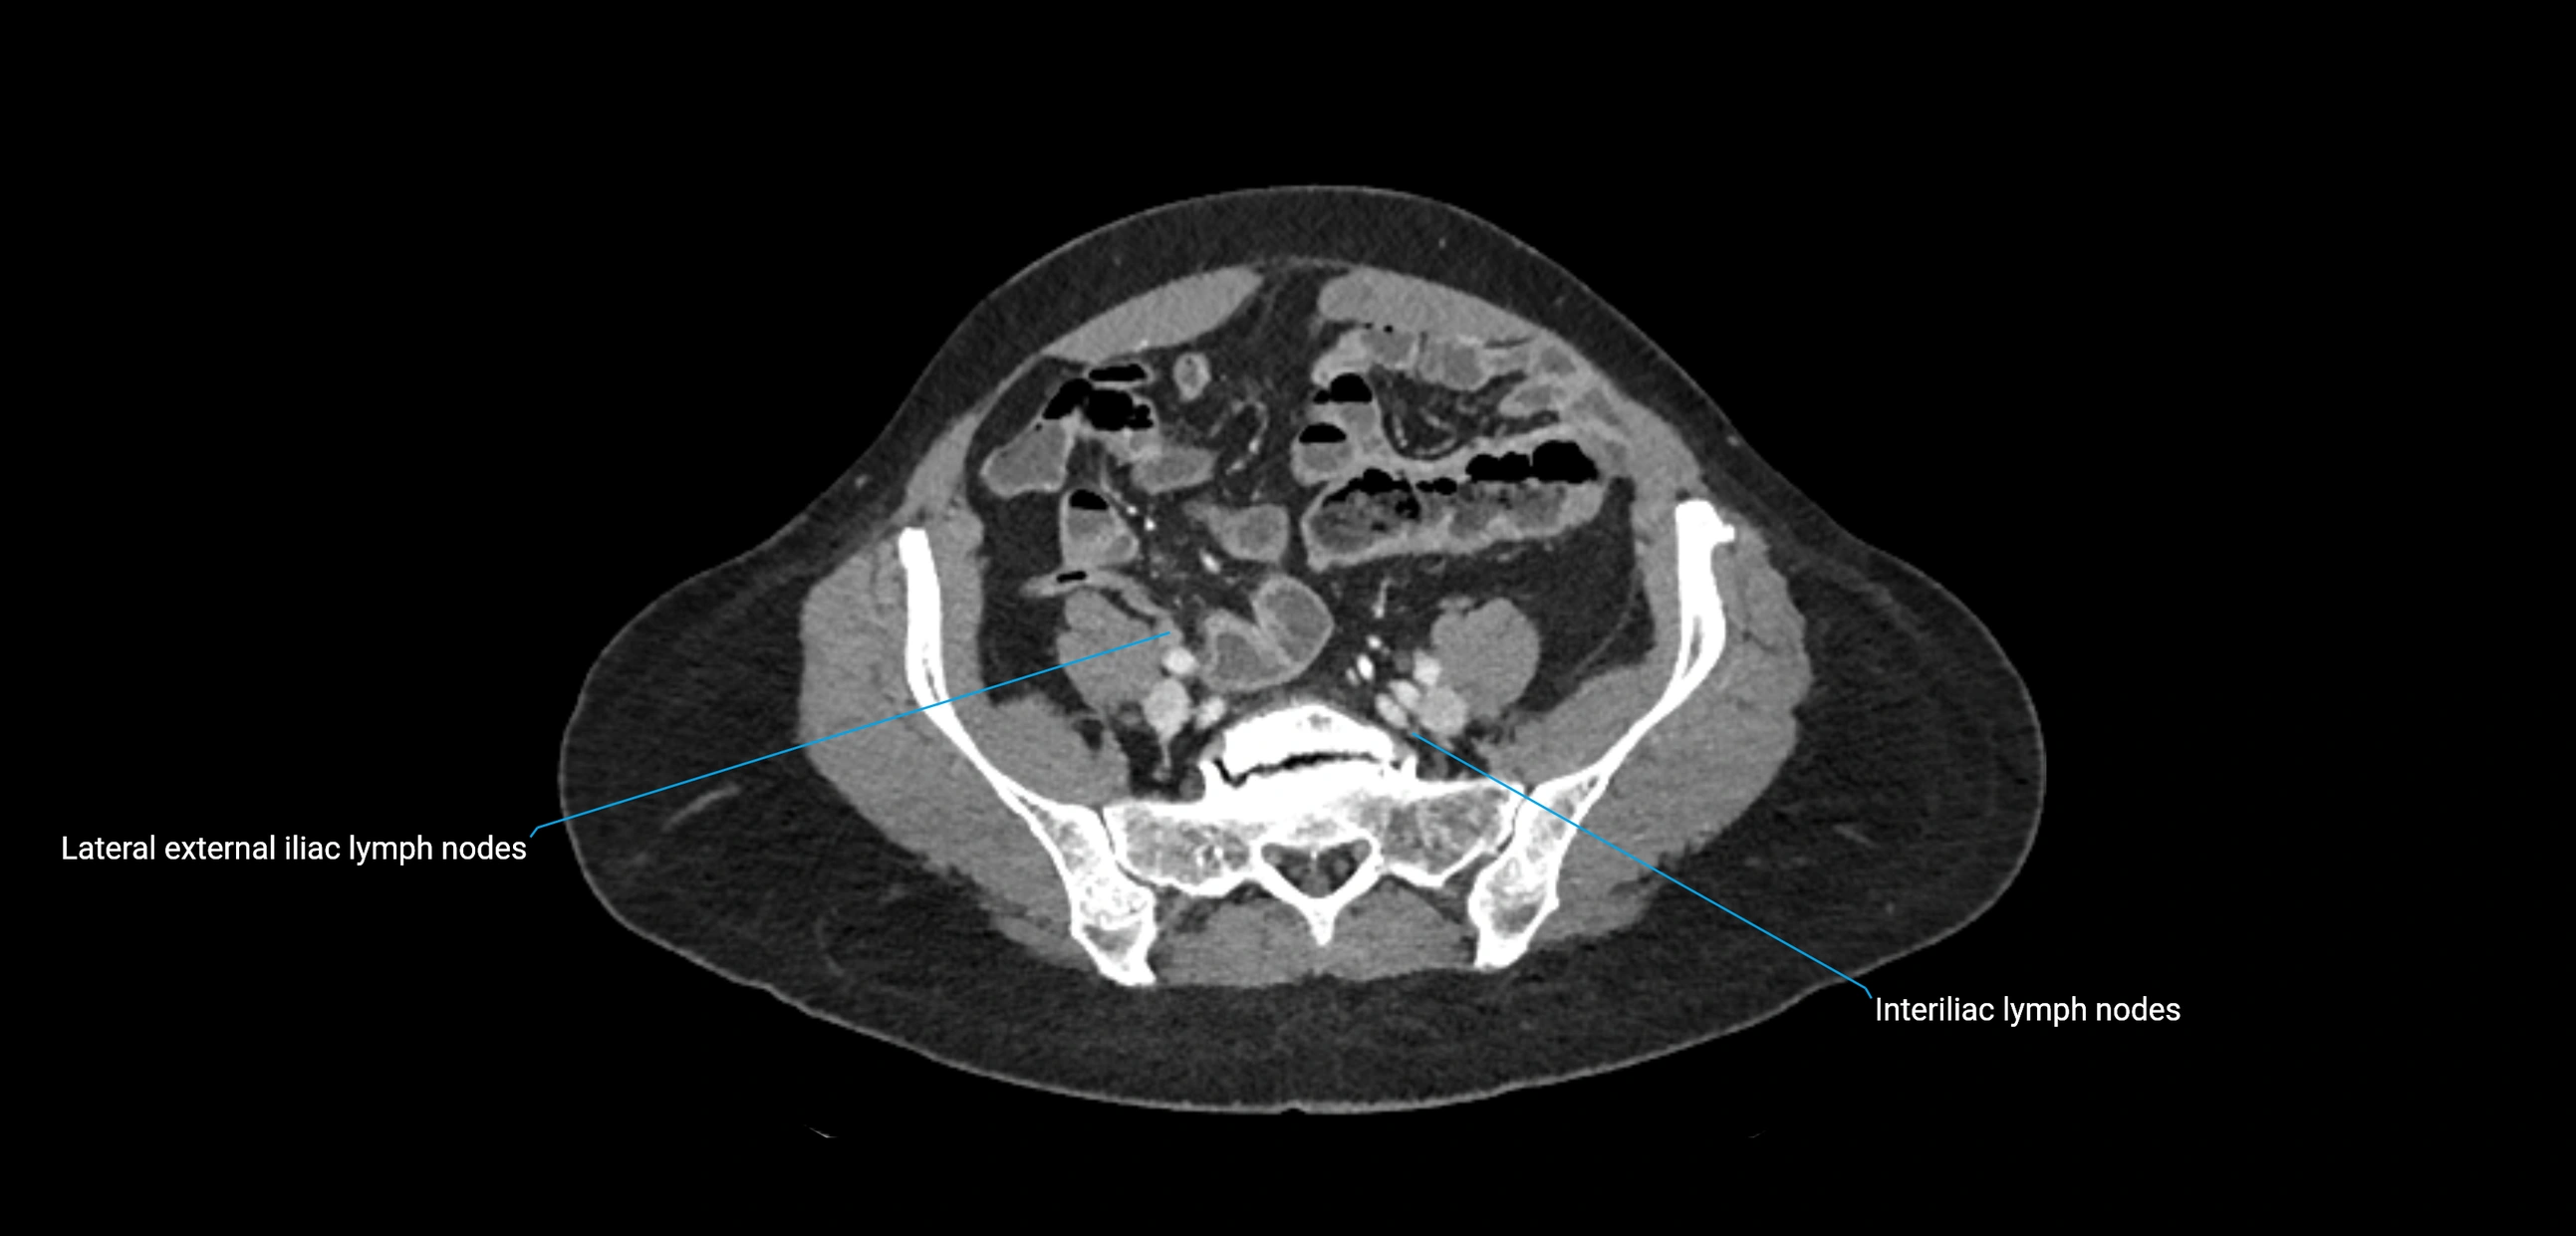

MRI images

image